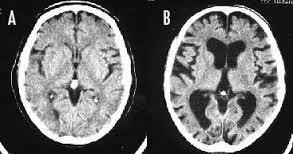

喫煙者のカキコが馬鹿ばかりな理由↓ 喫煙すると頭が悪くなるのは本当です。 長期の喫煙により大脳皮質が薄くなり、認知機能が低下してしまうのです。 画像Aは喫煙しない人の脳、画像Bは喫煙者の脳です。 画像Aの脳と比べて、画像Bの脳は萎縮して隙間だらけになっています。 喫煙をやめても元の状態まで回復するのに数十年かかるそうです。

--- 「喫煙者の脳」やはり異変が起きていた(石田雅彦) - Yahoo!ニュース ---

タバコを吸うと脳がすっきりするのは真っ赤な嘘だ。研究によれば喫煙者の脳では明らかに異常が起きている。認知機能も低下し、大脳皮質が元に戻るのには25年もかかる。一刻も早くタバコなど止めたほうがいい。